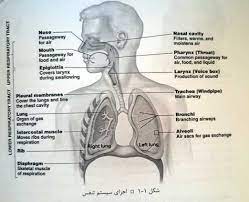

قیمت: 76٬000 تومان - دسته بندی فایل: پاورپوینتفیزیولوژی دستگاه تنفس

فروش ویژه پاورپوینت حرفه ای فیزیولوژی دستگاه تنفس با تخفیف استثنایی فقط 99 هزار تومان تعداد اسلاید: 125